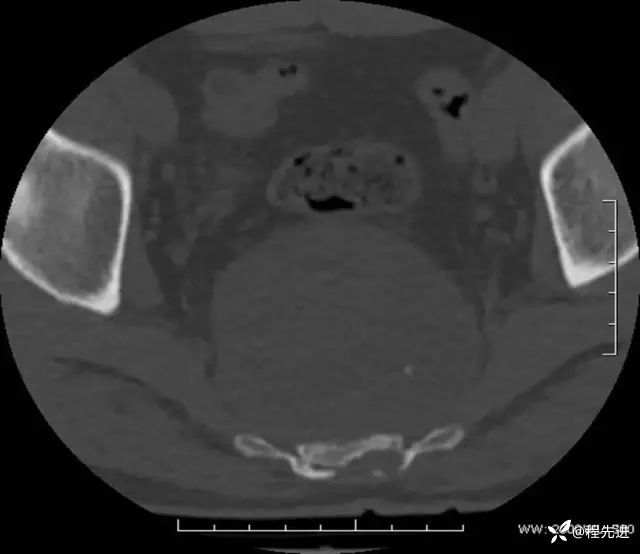

CT平扫:

骨窗: